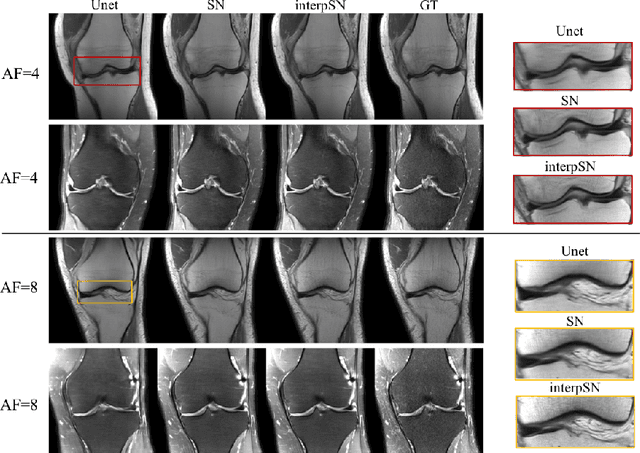

We present a deep network interpolation strategy for accelerated parallel MR image reconstruction. In particular, we examine the network interpolation in parameter space between a source model that is formulated in an unrolled scheme with L1 and SSIM losses and its counterpart that is trained with an adversarial loss. We show that by interpolating between the two different models of the same network structure, the new interpolated network can model a trade-off between perceptual quality and fidelity.